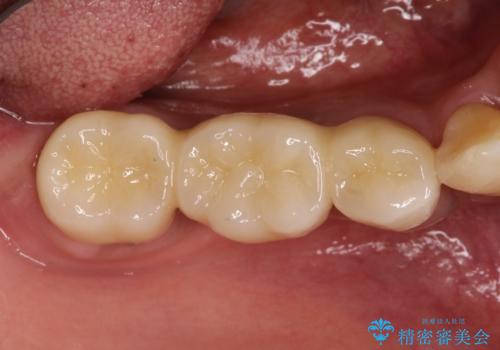

歯根の縦方向への破折は保存不可となることが多いです。

今回は抜歯後、オールセラミックにて修復を行うことで審美性の高い治療を行うことができました。